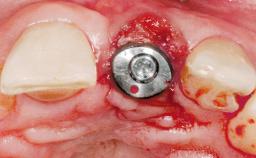

Immediate Placement of an Implant in a Maxillary Left Central Incisor Site

| Placement Protocol | Immediate implant placement |

| Tooth Site | Maxillary incisor or canine |

| Socket Morphology | Single-root socket |

| Socket Integrity | Damage to one or more bone walls |

| Bone Volume | Damage to one or more socket walls |